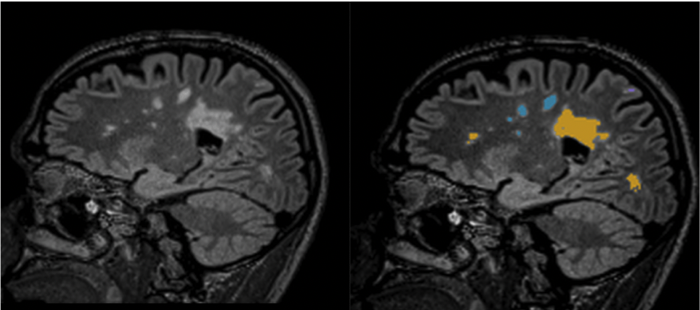

- MRI: An MRI can show lesions on the brain and spinal cord, which can be indicative of MS. Patients may also undergo a contrast MRI to highlight lesions when MS is in an active phase.

To enhance your care, ImageCare has introduced icoBrain Artificial Intelligence which helps diagnose Multiple Sclerosis. icoBrain MS provides clinicians with easy-to-interpret reports to support the detection of MS and can compare changes of white matter lesions between current and previous exams. The exam does not require an extra authorization or an additional charge. It will be run on all patients exhibiting symptoms of MS or patients under 50 years of age exhibiting numbness, tingling or loss of sensation. This sequence does not require an additional precertification nor will the patient incur any additional costs.